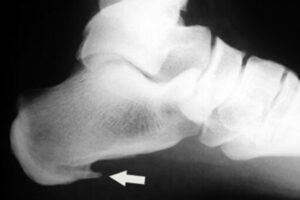

Fascite plantare o sperone calcaneare?

Spesso vengono confuse. Lo sperone calcaneare è una calcificazione visibile con radiografia nel punto di inserzione della fascia. Se non vi è calcificazione, si tratta di fascite plantare.

Entrambe hanno sintomi e trattamenti simili. Lo sperone si sviluppa per una trazione prolungata della fascia: ecco perché è importante trattare precocemente la fascite per evitarne la formazione.